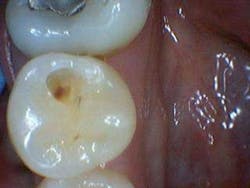

In the aforementioned case, the reading on the occlusal surface was a 46 (see Figs. 3 through 8 below). Look at what was underneath. Surprised? I often wonder how many times per day lesions like this are going undiagnosed.

After the final smear layer was removed, the tooth was filled with Grandio resin. Afterwards, I showed the photographs to my patient. Any doubt that he had was immediately erased. Most importantly, he was grateful and his trust in me was solidified.